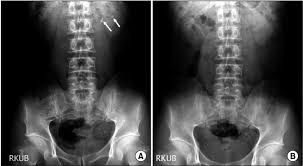

X Ray Kub Of A Patient With Bilateral Renal Stones Large Renal Shadows Download Scientific Diagram

X Ray Kub Of A Patient With Bilateral Renal Stones Large Renal Shadows Download Scientific Diagram from www.researchgate.net

There was no significant difference in measured size between kub and ct p 0 11. Do all kidney stones show up on a kub kidney xray. Combining ultrasound with a kub while not as sensitive or specific as a ct scan does do a pretty good job of picking up clinically significant stones.

Patients with serum creatinine 1 8 mg dl were. The other common study for kidney stones are plain x rays of the abdomen known as kub s which stands for kidney ureter bladder. Patients with serum creatinine 1 8 mg dl were. We then compared accuracy of stone measurement from kub with ct.